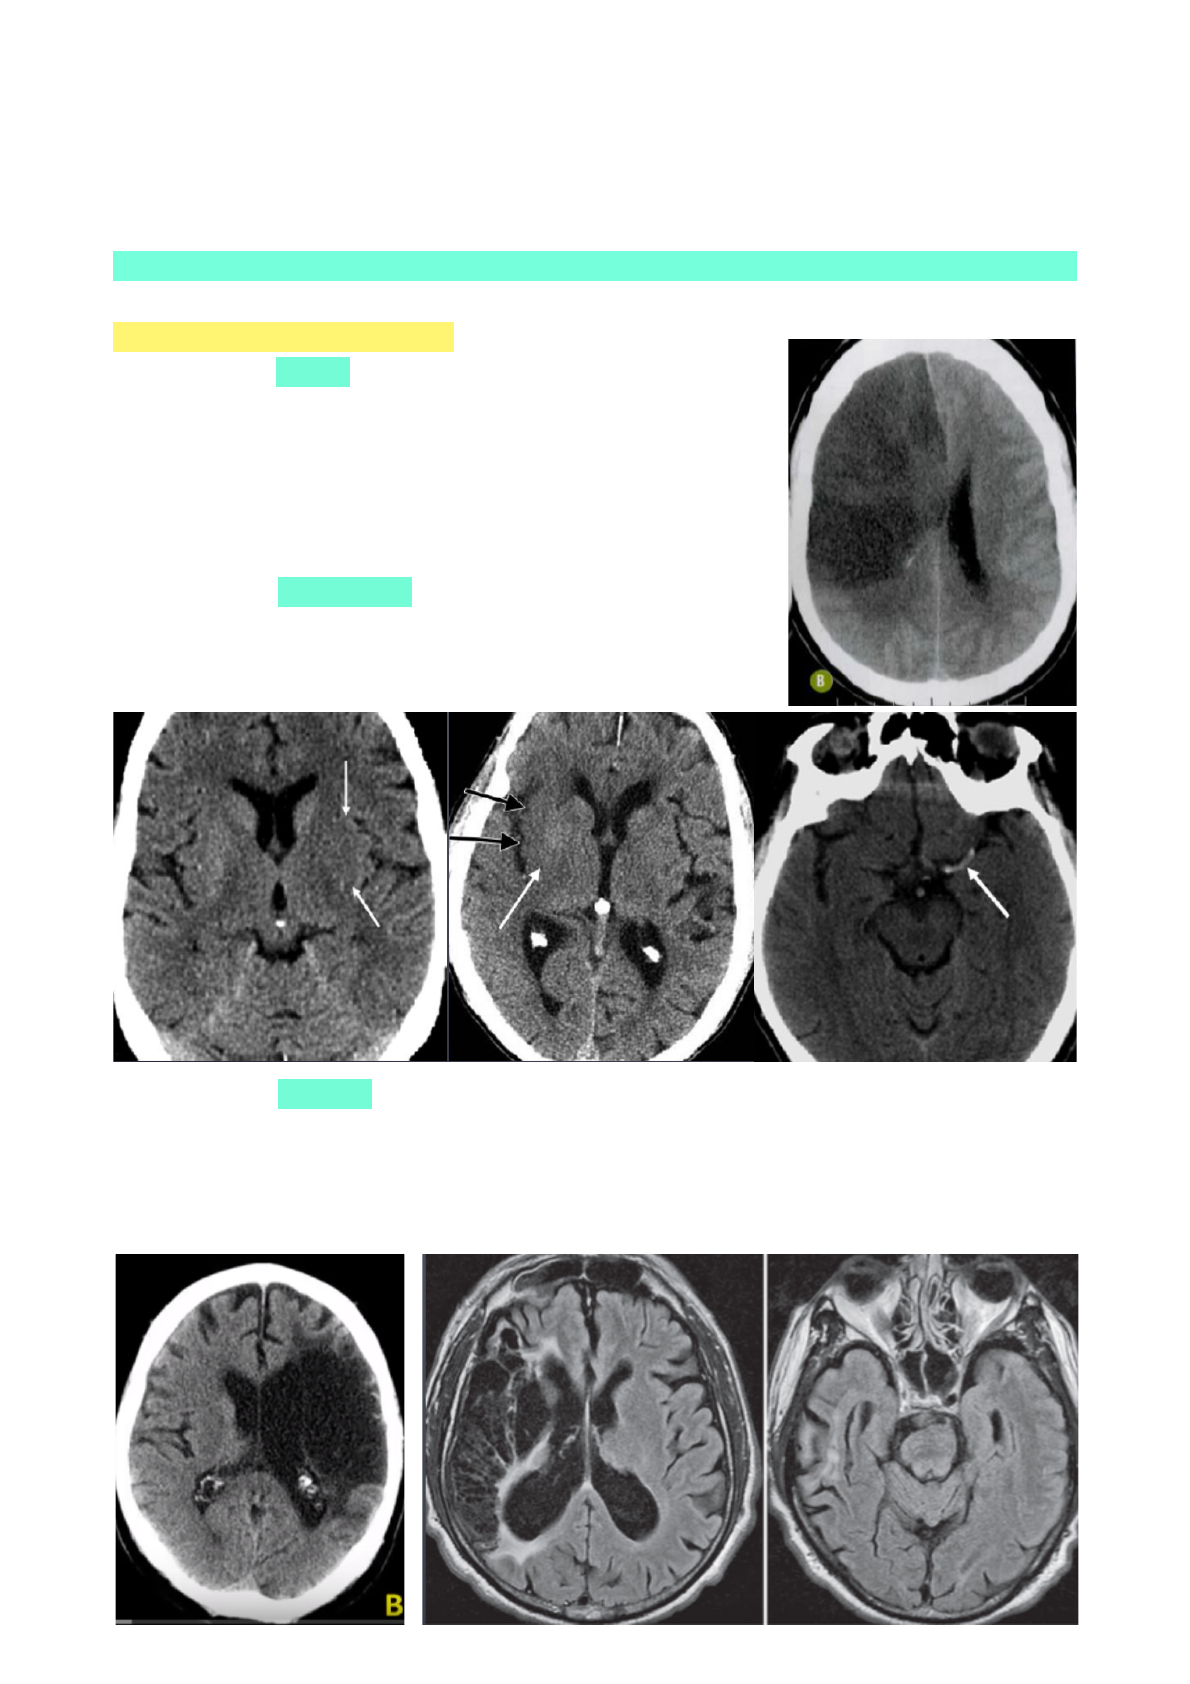

ACIDENTE VASCULAR ENCEFÁLICO

• É quando ocorre um distúrbio no fluxo sanguíneo, gerando uma perda súbita de função. Pode ser

ISQUÊMICO (redução ou paralisação do fluxo) ou HEMORRÁGICO (ruptura vascular).

AVE ISQUÊMICO

• AVE isquêmico é causados por uma obstrução nas artérias do cérebro.

TOMOGRAFIA COMPUTADORIZADA:

AVE ISQUÊMICO AGUDO: são sinais que aparecem em 24 horas

• Edema citotóxico

• Apagamento da diferenciação córtico-subcortical

• Efeito expansivo (diminui sulcos)

• Hipodensidade na região isquemiada

• Desvio da linha média

AVE ISQUÊMICO HIPERAGUDO: são sinais que aparecem em 6 horas

• Núcleo lentiforme obscurecido

• Sinal da fita insular (perda da diferenciação)

• Sinal da arteria hipertensa (por conta do trombo)

AVE ISQUÊMICO CRÔNICO:

• Fenômeno ex-vácuo (aumento ventricular ipisilateral)

• Encefalomalácea (efeito cicatricial)

• Líquor ocupa o local degenerado

• Pode levar a demência vascular

AVE HEMORRAGICO

• O AVE hemorrágico se caracteriza pelo sangramento em uma parte do encéfalo, em consequência do

rompimento de um vaso sanguíneo. Pode ocorrer para dentro do cérebro ou tronco cerebral (hemorrágico

intraparenquimatoso) ou para dentro das meninges (hemorragia subaracnóidea).

* EPICENTRO: onde está o hematoma.

TOMOGRAFIA COMPUTADORIZADA: pode afastar a hipótese de hemorragia.

RESSONÂNCIA MAGNÉTICA: pode ver os focos hemorrágicos de AVE isquêmicos, principalmente no T2 e

gradiente eco (GRE).

* HEMORRAGIA SUBARACNOIDEA: sangue ocupa os sulcos, cisternas, fissuras… É uma sangue extra-

axial.

* HEMORRAGIA SUBDURAL: encontra-se embaixo da dura-mater (entre a dura e a aracnoide). É côncavo-

convexo - geralmente é sangramento VENOSO.

* HEMORRAGIA EPIDURAL: entre a dura e a calota craniana. É biconvexo - geralmente ARTERIAL, dessa

forma, pode ser mais rápido.